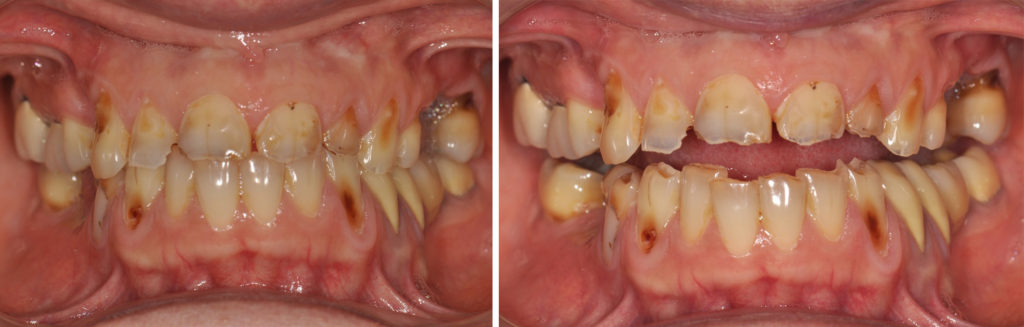

Fig. 2a à 2f : vues intra-buccales de la situation initiale

Analyse dentaire :

• les dents 14, 25, 26, 36 et 46 ont toutes été extraites pour des raisons de délabrements des tissus dentaires (et non pas pour des raisons parodontales),

• les dents 17 et 16 sont dévitalisées et porteuses de coiffes céramo-métalliques dont les limites vestibulaires sont exposées. La dent 36 est remplacée par un bridge céramo-métallique de 4 éléments en appui sur les dents 34, 35 et 37 (dévitalisées),

• les dents 11, 22, 27, 44, 45 et 47 présentent des obturations coronaires en composite qui présentent des signes d’infiltration,

• toutes les les autres dents présentent des signes d’érosion avancée avec des plages d’exposition dentinaires, larges par endroit, vestibulaires, linguales et/ou occlusales.

Analyse parodontale :

On ne note pas de signes – ni cliniques, ni radiologiques – de maladie parodontale (pas de poches, pas de mobilités…).

Le biotype parodontal est fin. On note des récessions gingivales sur les dents et dont certaines sont très proches de la ligne de jonction muco-gingivale. L’alignement des collets des incisives maxillaires est asymétrique.